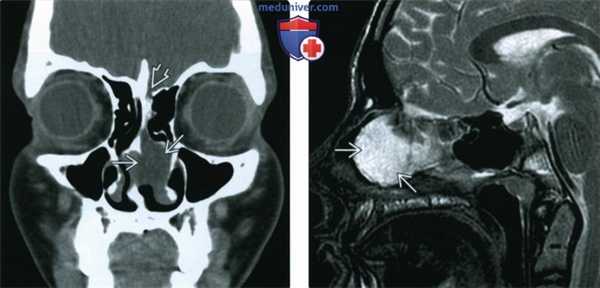

(Слева) При аксиальной КТ в костном окне у новорожденного со срединным мягкотканным объемным образованием лба визуализируется крупный передний дефект черепа, сквозь который выбухает большая лобно-носовая мозговая грыжа.

(Справа) При 3D-реконструкции поверхности (вид спереди, КТ) у этого же пациента визуализируется большое фронтоназальное цефалоцеле между глазами, выбухающее через открытый лобный родничок.

(Слева) При корональной КТ без КУ у пациента с назоэтмоидальным цефалоцеле визуализируется гиподенсное образование в полости носа слева. Мелкий дефект в основании черепа весьма сложно различить в мягкотканном окне.

(Справа) При сагиттальной МРТ Т2 FS в цефалоцеле у этого же пациента определяется сигнал, преимущественно соответавующий ликвору. На этой томограмме паренхимы мозга внутри цефалоцеле не определяется.

(Слева) При аксиальной КТ в костном окне у ребенка в возрасте 17 месяцев визуализируется экспансивное образование в верхних отделах полости носа и решетчатой области, сопоставимое с цефалоцеле назоэтмоидального типа. Большой дефект основания черепа был обнаружен на корональных томограммах (не показаны).

(Справа) При сагиттальной MPT Т2 FS у этого же пациента определяется выбухание паренхимы головного мозга и оболочек сквозь дефект в передних отделах основания черепа (назоэтмоидальное цефалоцеле).